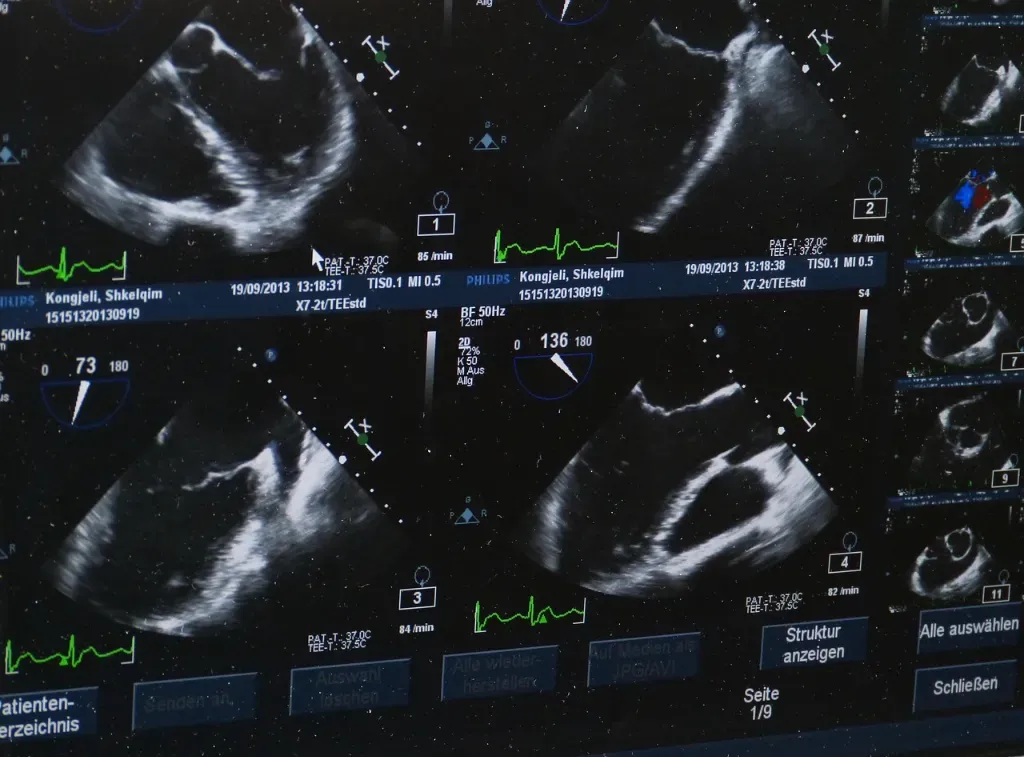

Badanie USG, czyli ultrasonografia, to jedna z podstawowych i najczęściej wykorzystywanych metod diagnostycznych w medycynie. Polega na zastosowaniu fal ultradźwiękowych, które pozwalają na uzyskanie obrazu narządów wewnętrznych w czasie rzeczywistym. Dzięki temu specjalista może obserwować struktury anatomiczne pacjenta bezpośrednio na ekranie urządzenia, co znacząco ułatwia ocenę ich stanu i funkcji.

Podczas badania na skórę nakładany jest specjalny żel, który poprawia przewodzenie fal ultradźwiękowych i umożliwia uzyskanie wyraźnego obrazu. Specjalista, posługując się odpowiednią głowicą, dokładnie bada interesujące obszary ciała, analizując ruch i strukturę tkanek. Warto podkreślić, że badanie USG pozwala nie tylko na ocenę obecności zmian, ale również na monitorowanie ich rozwoju czy skuteczności leczenia.

Następnie na skórę nakładany jest specjalny żel, który ułatwia przewodzenie fal ultradźwiękowych. Lekarz, korzystając ze specjalnej głowicy, dokładnie skanuje wybrane obszary ciała. Obraz pojawia się na ekranie w czasie rzeczywistym, co pozwala na ocenę ruchu oraz struktury tkanek. W zależności od sytuacji, badanie może być powtarzane, jeśli specjalista uzna to za konieczne.